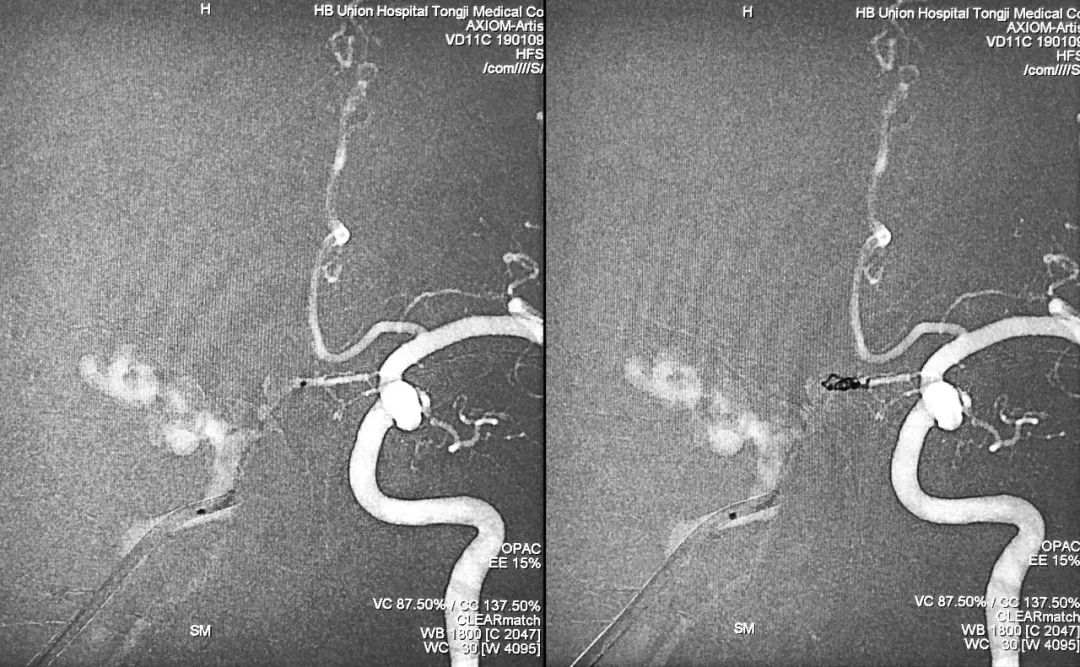

⑦ 术后左颈总动脉正、侧位造影显示瘘口不显影:

将造影管移入右侧颈总动脉,正、侧位造影显示瘘口不显影:

术后正、侧位蒙片显示伊维尔-Ⅰ胶在右侧海绵窦内的铸型(约6 ml):